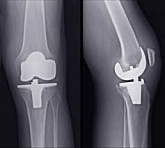

Еndoprosthesis of knee joint

In the late stages of arthrosis of the knee joint, accompanied by a pronounced restriction of the volume of movements, constant intense pain, deformity of the limb, the only way to recover is to replace the affected joint with an artificial joint - arthroplasty.

This method allows you to return the correct form of the limb, the full volume of movements in the joint, relieve the constant pain and crunch during movements and, as a result, significantly improve the patient's quality of life.

Below are presented X-ray photographs and photographs, illustrating the amount of motion in the affected joint before and after surgery.